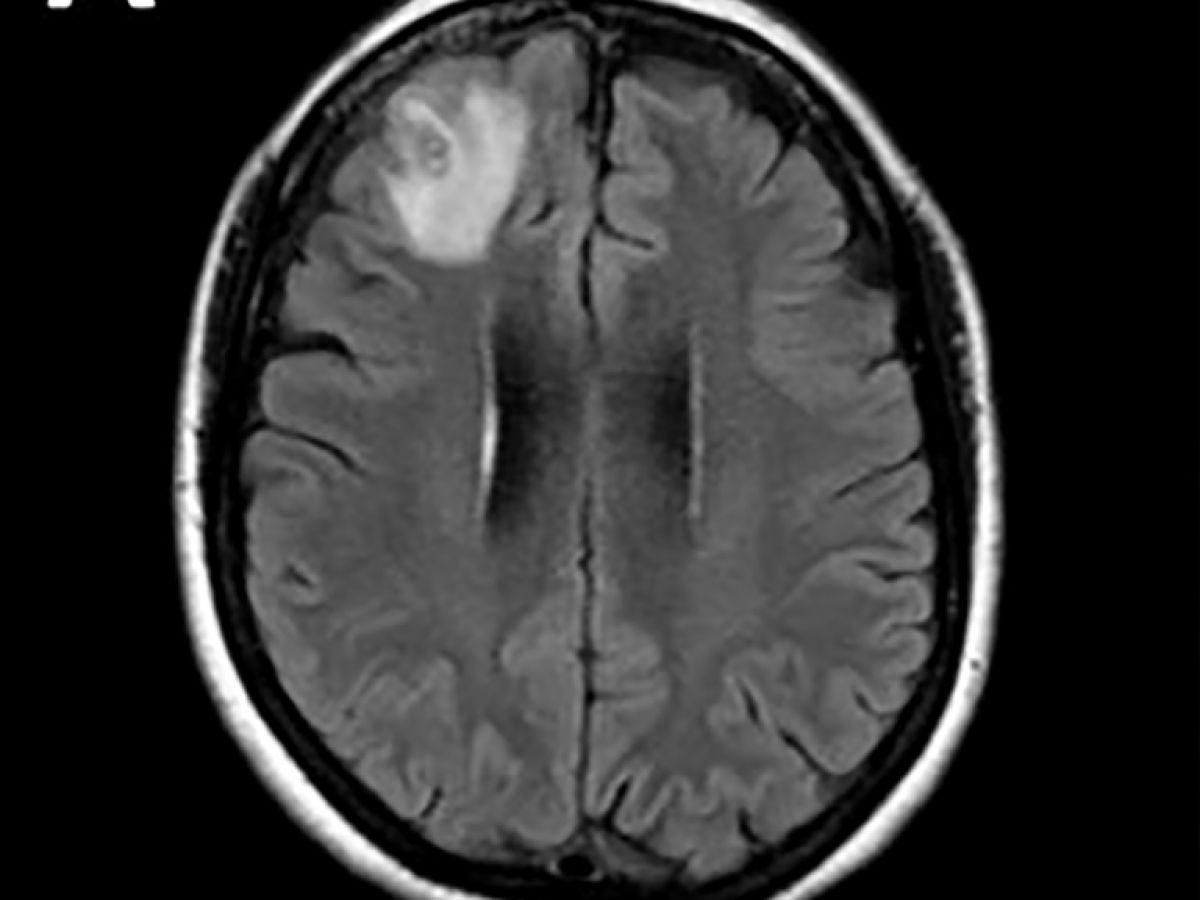

Africa-Press – Togo. Un ver rond, qui parasite généralement les serpents, a été découvert pour la première fois sur un être humain. Il a été extrait « vivant et se tortillant » du cerveau d’une Australienne lors d’une intervention chirurgicale, ont annoncé mardi des médecins australiens. Les médecins ont découvert une « lésion atypique », grâce à un examen IRM, dans la partie frontale du cerveau de cette femme âgée de 64 ans qui souffrait de pertes de mémoire.

« À notre connaissance, c’est également le premier cas impliquant le cerveau d’une espèce de mammifère, humaine ou autre », a-t-il précisé. Cette découverte a fait l’objet d’un article dans la revue « Emerging Infectious Diseases ». Les scientifiques pensent que l’Australienne a été parasitée par des plantes comestibles, probablement contaminées par des larves présentes dans des excréments de serpents. Le parasite, dont la « structure en forme de fil » est apparue sur les scanners cérébraux, a ensuite été identifié grâce à des tests ADN. « Il n’est jamais facile ni souhaitable d’être le premier à être malade de quoi que ce soit au monde », a ajouté le Dr Senanayake, « je ne saurais trop exprimer notre admiration pour cette femme, qui a fait preuve de patience et de courage tout au long de ce processus. » Selon le Dr Senanayake, il est « probable que d’autres cas soient identifiés à l’avenir ».